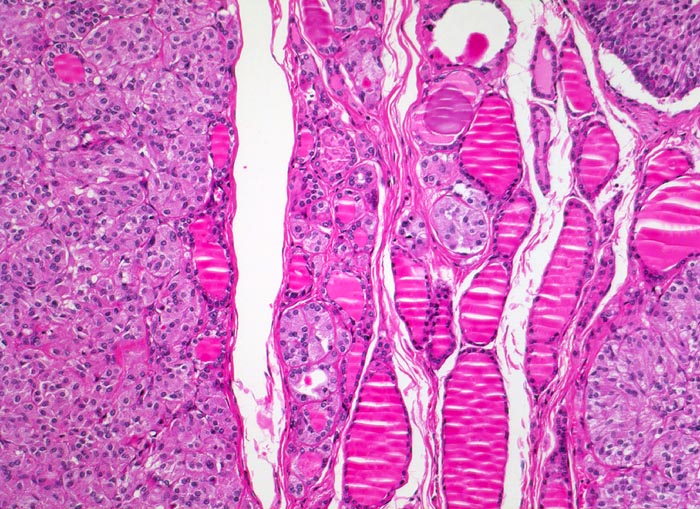

medulläres Schilddrüsenkarzinom bei MEN 2A

Überwiegend solide Tumorknoten aufgebaut aus relativ monomorphen Zellballen, zwischen denen schmale Bindegewebssepten verlaufen. Zwischen den Tumorknoten ist normales Schilddrüsenparenchym mit Herden von hyperplastischen C-Zellen erkennbar.

Mehrere scharf begrenzte weisse Knoten in beiden Schilddrüsenlappen von bis zu 8mm Durchmesser.

Beim Vater der Patientin wurde ein bilaterales Phäochromozytom diagnostiziert und in der Folge eine multiple endokrine Neoplasie vom Typ 2A. Im Familienscreening wurde bei der Patientin eine Mutation im Ret-Protoonkogen nachgewiesen und eine prophylaktische Thyreoidektomie durchgeführt.

100